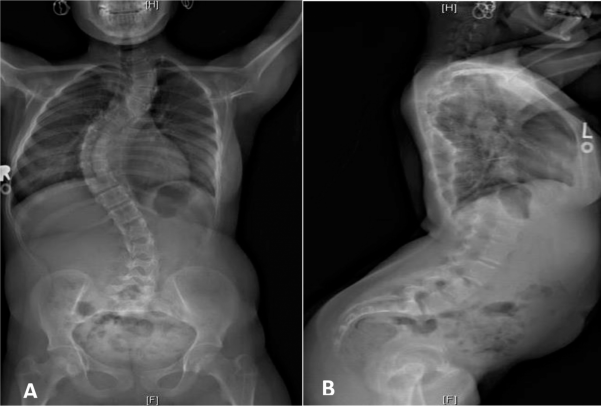

Fig.5. Vistas posterior e lateral da coluna vertebral aos 13 anos, mostram escoliose toracolombar multisegmentária com levoscoliose torácica superior, dextroscoliose torácica inferior e levoscoliose lombar. Fonte: Lymphosign.com